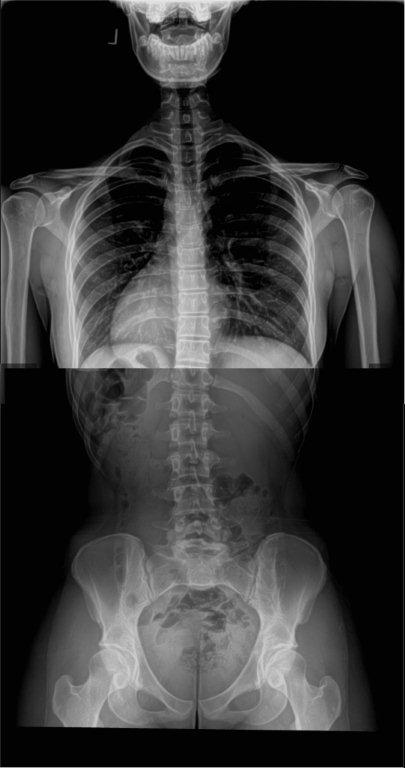

Along with my malalignment story, I would like to share some details pertaining to my daughter, Ally, at age 18 regarding her SI dysfunction and its related malalignment syndrome . Click on X-rays to enlarge.

Here are the diagnostic findings on her full spine x-rays provided by Dwyer Chiropractic Center:

- Sacral apex angle of 24 degrees (normal is 45 degrees)

- 6 degree angle on L5 (normal is 10-15)

- 1mm of anterior rotation and 7 mm of internal rotation on her left ilium

- 4mm of posterior rotation on her left side of sacrum

- Mild left lateral curve in her lumbar region, even leg length upon analysis (also confirmed by prior limb length study), reverse cervical curve

IMPRESSION:

- Left pelvic subluxation

- Posterior and Inferior L5 subluxation

- Posterior sacral apex with left posterior rotation

- Healed L3 spinous tip fracture

- Reverse cervical curve with anterior head carriage